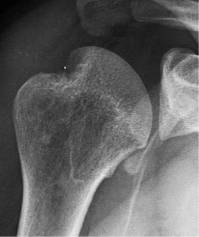

需要在肩关节内旋位、中立位、外旋位时分别拍摄3张正位X线,来评估有无Hill-Sachs损伤。

中立位